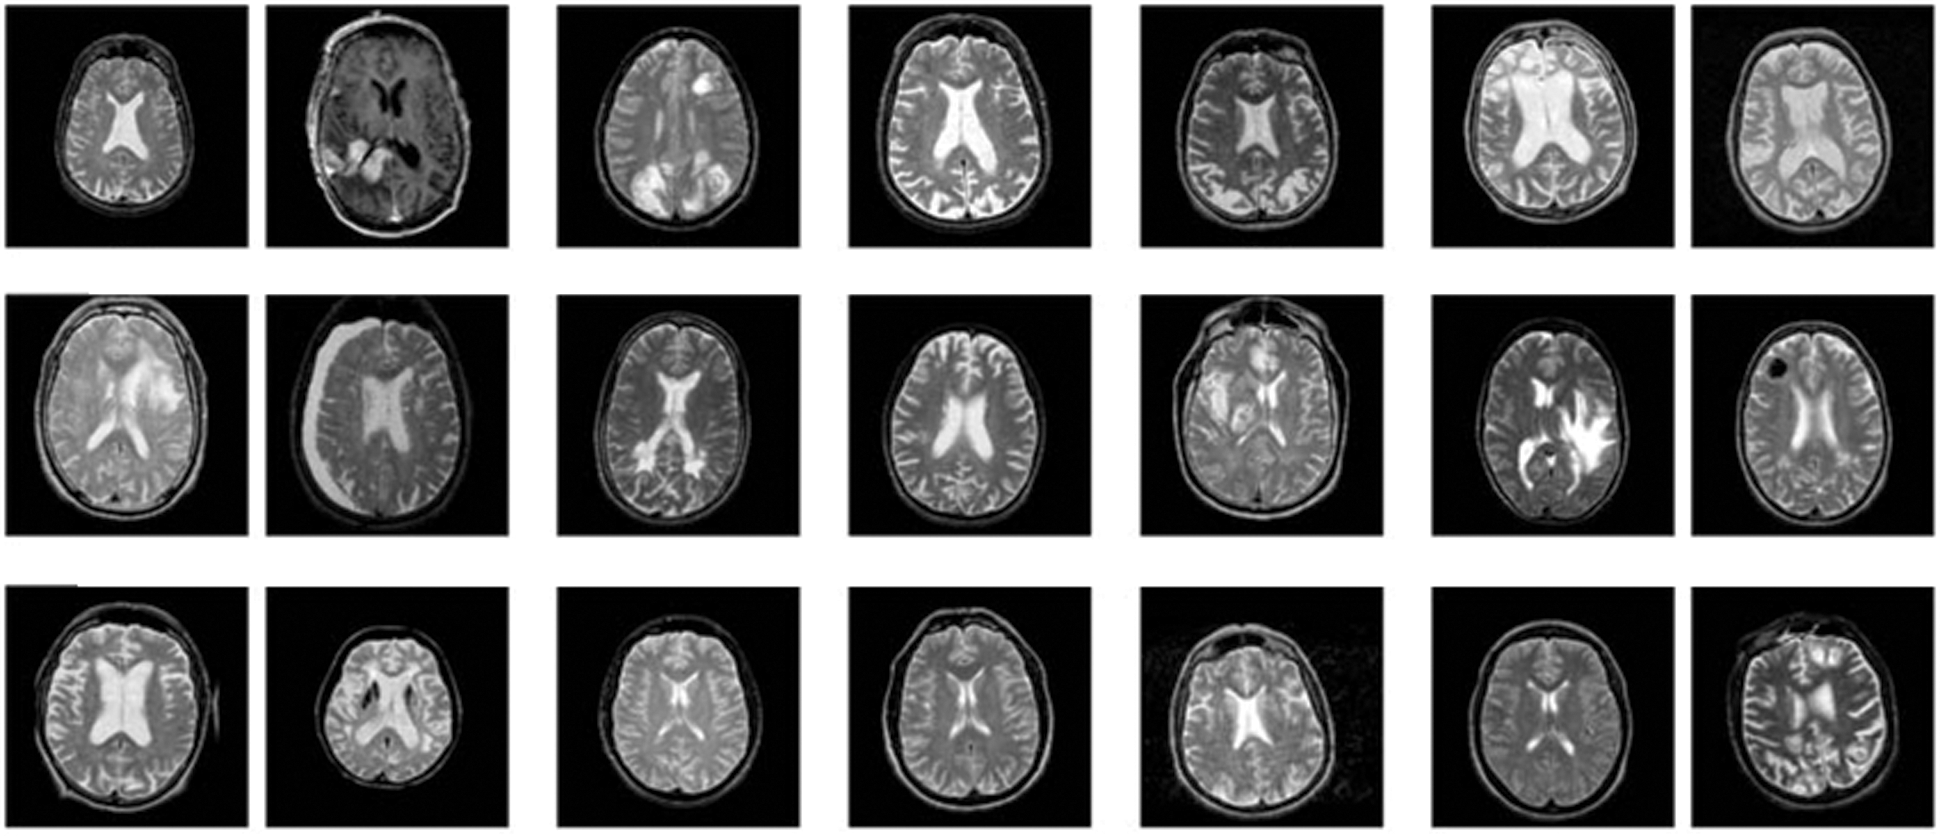

This section examines the performance analysis of the ORB-OANN technique on the diagnosis of AD. The dataset utilized to train our model was gathered from OASIS. The site suggestions a public data repository for study resolves. The dataset covers the cross-sectional brain MRI scan of different issues from the age of 18–96. An image was covering image in the sagittal, coronal, and axial planes of human brain. For testing the presented technique, MRI scan in the smart CT scanner was developed that are utilized at several hospitals linked on the Internet. Fig. 3 illustrates some sample images.

Figure 3: Sample images